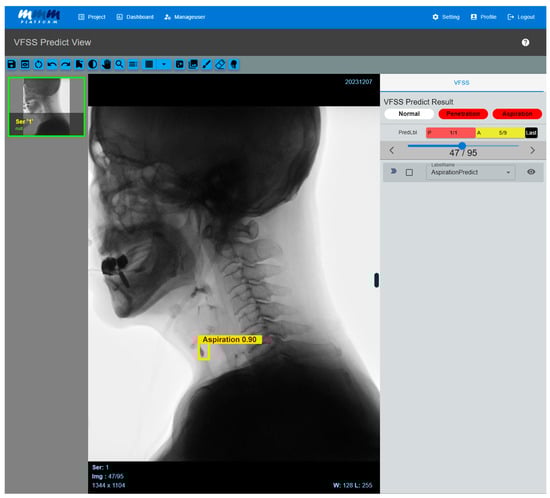

When VFSS videos contained a large number of frames due to long recording times, they were divided into multiple series using a self-developed DICOM conversion tool, with a maximum of 500 frames per series. Individual frames were extracted from each divided series as JPG format images, and the extracted images were converted to grayscale to preserve the fluoroscopic characteristics of the videos. Afterwards, they were resized to 960 × 960 pixels to match the model input size. The labeling process was carried out in the same manner as on the previously developed web-based labeling platform [21]. The preprocessed frames were then input into a trained AI model to predict the aspiration, penetration, or no airway invasion. Finally, the prediction results were overlaid on the original video frames in the form of bounding boxes for visual verification and analyzed based on the predicted outcomes (Figure 4).

Figure 4. Multi-frame medical image-labeling web application. When a VFSS video is uploaded to an application equipped with the developed AI model, the system automatically analyzes the video and classifies it into penetration or aspiration. If the AI model detects abnormal signs of aspiration, it visually highlights the corresponding frame by displaying a bounding box and confidence value. Users can directly review the AI model’s prediction results, and the system processes the uploaded video frame by frame, providing the detected areas in a time-synchronized manner along with the original video. As a result, clinicians can intuitively identify the exact moments when abnormal findings are detected while playing the video.